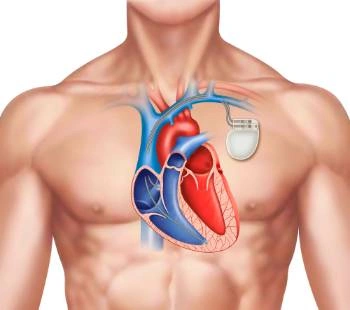

Supera los desafíos de salud cardiovascular con la ayuda de nuestros especialistas en Cardiología Intervencionista en Tabasco.

¡En Tabasco, el Dr. Carlos Aguila Bravo destaca como un cardiólogo intervencionista que utiliza métodos actualizados en cardiología! No todos los especialistas en la región se mantienen al día con las últimas técnicas practicadas en países de primer mundo, pero el Dr. Aguila Bravo es diferente. Con su compromiso en brindar la mejor atención cardiológica, te ofrece una experiencia médica vanguardista y actualizada. No te conformes con menos cuando se trata de tu salud cardiovascular. Agenda tu consulta con el Dr. Carlos Aguila Bravo en Tabasco y descubre cómo su enfoque innovador puede marcar la diferencia en tu bienestar. ¡Tu corazón merece lo mejor y él se asegurará de brindártelo!